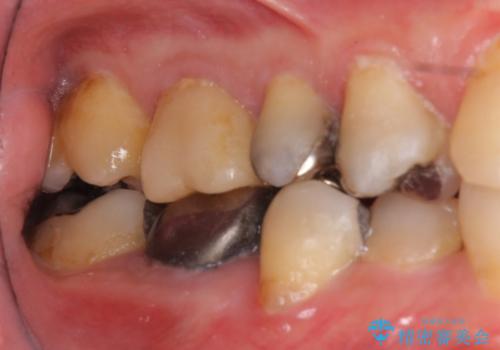

⑵歯周外科手術

⑶5−6か月待つ

今回は、歯周外科手術を行い、歯ぐきの厚みを薄くし、また、歯槽骨の高さも整えて、歯周環境を整えました。